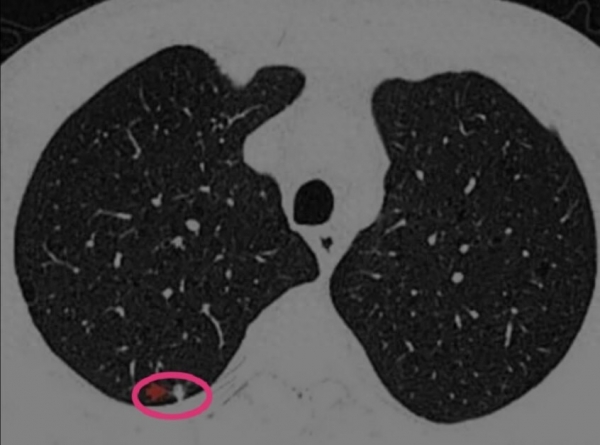

62 岁的王先生,感染新冠康复后一直咳嗽不断,总感觉胸口发闷,稍微活动就气短,还时不时咳出白黏痰。去医院检查发现双肺多发结节,最大的直径达 8mm,报告提示为炎性结节。

坚持治疗两个月后,王先生咳嗽、胸闷症状明显减轻,咳痰量也少了很多。三个月复查 CT,惊喜地发现最大的结节缩小到 4mm,其他小结节也有不同程度减小。后续通过调整药方巩固治疗,半年后再复查,结节基本消失。